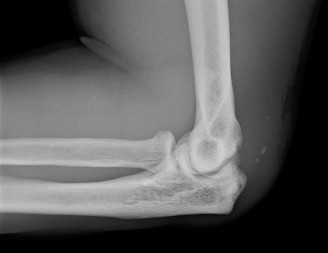

It should be noted that reverse total shoulder arthroplasty is also the procedure of choice in patients with cuff-tear arthropathy (aka rotator cuff arthropathy). Characteristics of cuff-tear arthropathy include superior migration of the humerus due to a massive rotator cuff tear, glenohumeral joint destruction, subchondral osteoporosis, and humeral head collapse (see Fig. 2–17). A reverse total shoulder

Figure 2–17_X-rays of a patient showing evidence of cuff tear arthropathy. The humerus is migrated superiorly, the glenohumeral joint is destroyed, there is subchondral osteoporosis, and the humeral head is collapsed. (From Ecklund KJ, Lee TQ, Tibone J, Gupta R. Rotator cuff tear arthropathy. _J Am Acad Orthop Surg. 2007;15(6):340–349.)